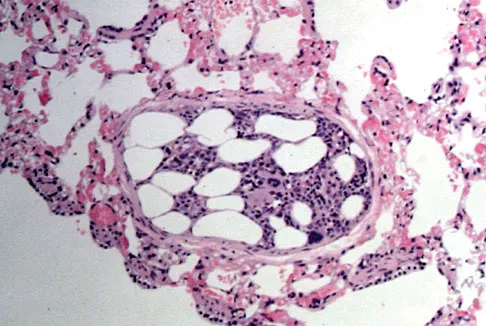

Embolic material generated during total knee arthroplasty (TKA) shown in Figure 29 is composed of which of the following substances?

Explanation